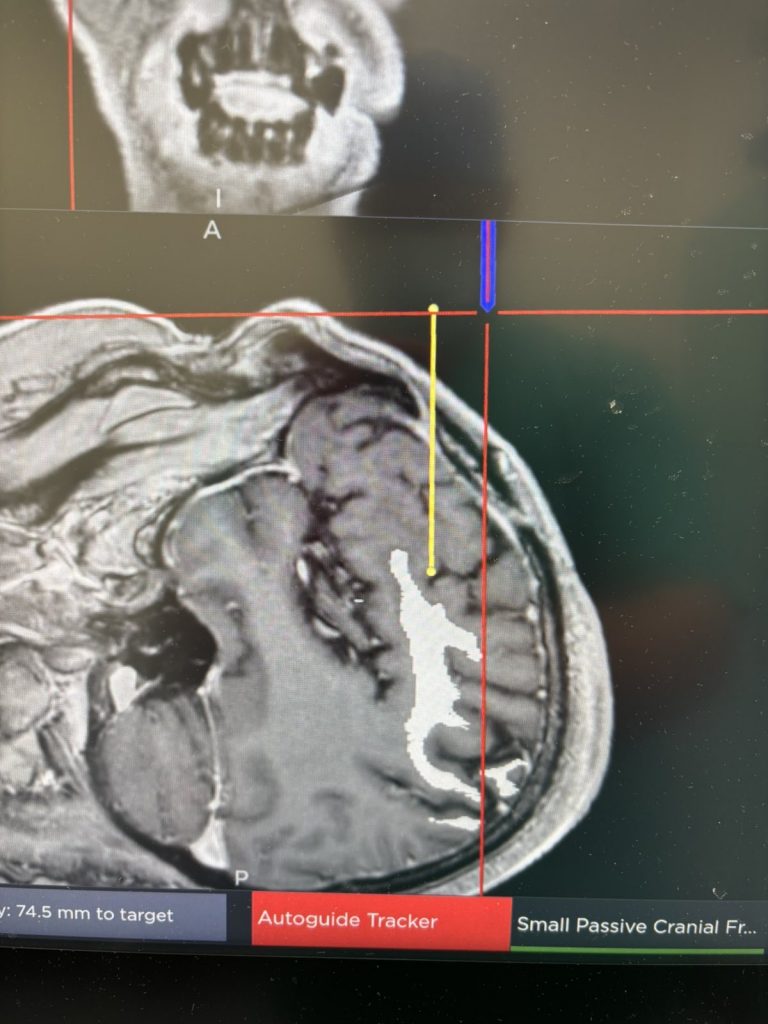

Το πλεονέκτημα του λέιζερ, πέραν του ότι είναι πολύ λιγότερο επιβαρυντικό για τον ασθενή, είναι ότι η επέμβαση ουσιαστικά πραγματοποιείται στον μαγνητικό τομογράφο και έχουμε τη δυνατότητα να παρακολουθούμε το αποτέλεσμα σε πραγματικό χρόνο (real time).

Στην προκειμένη περίπτωση η βλάβη καταστράφηκε πλήρως.